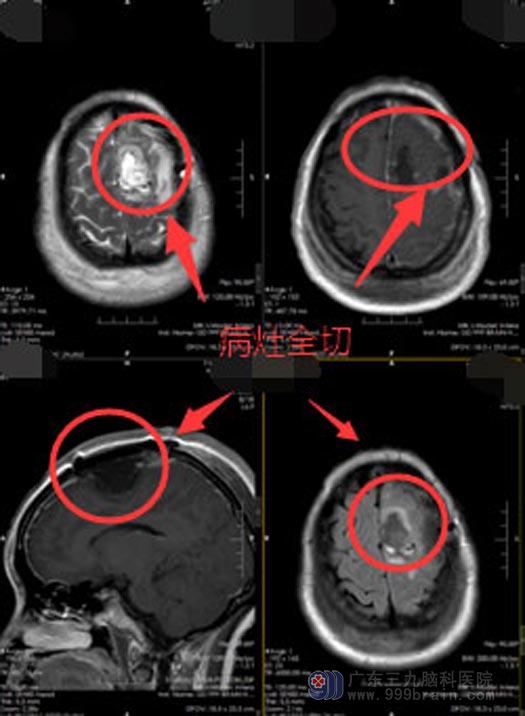

术中小陈唤醒成功,配合默契,荧光显微镜下全切肿瘤,肢体运动功能及语言功能保护好,术后未出现神经功能障碍,也没有出现癫痫发作,复查头颅mr肿瘤完全切除,已康复出院。

手术后